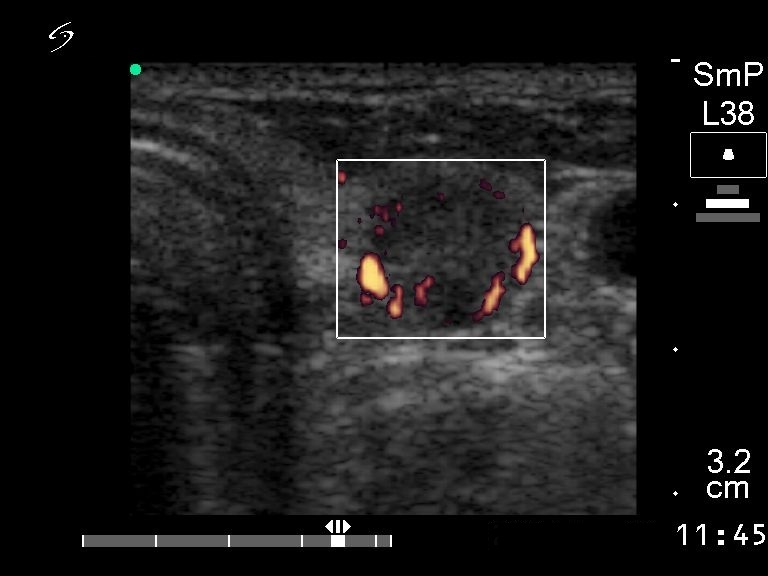

Ultrasonography. There was a solitary hypoechogenic nodule in the left lobe.